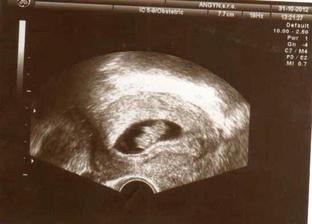

31.10.2012 - 9tt. návšteva poradne, USG, bábo rastie, vypísaná tehotenská knižka